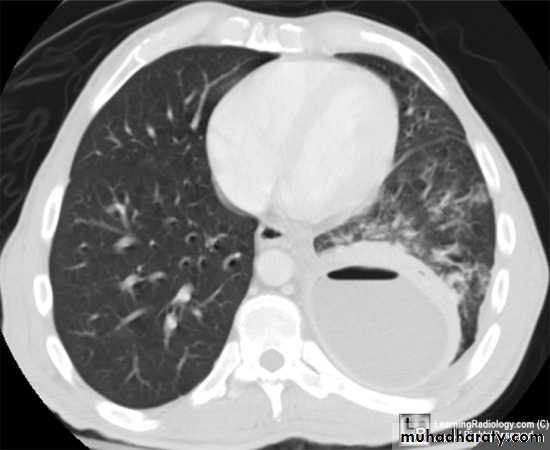

High resolution CT (HRCT) can be helpful in minimizing the differential diagnosis:

• Focal opacification favours bacteria, mycobacteria and nocardia

• Bilateral opacification favours PCP, fungi, viruses and nocardia

• Cavitation suggest mycobacteria, fungi and nocardia

• Pleural effusion suggests bacteria